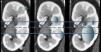

El componente A no suma en el cálculo de la nefrometría de la lesión. Se establece tomando como referencia la línea media renal en las imágenes axiales, siendo esta línea paralela a la dirección de las estructuras hiliares. Si el tumor es anterior a la línea media renal, se agrega el sufijo a; pero si es posterior, se añade una p (fig. 8).

(a) Hombre de 61 años de edad con carcinoma de células claras de 3,5cm (flecha) localizado por delante de la línea media renal (línea blanca) del riñón izquierdo. RS: 1+2+3+a+3=9a (mediana complejidad quirúrgica). (b) Hombre de 73 años de edad con carcinoma de células claras de 3,4cm (flecha) localizado por detrás de la línea media renal (línea blanca) del riñón derecho. RS: 1+2+2+p+2=7p (mediana complejidad quirúrgica).

Esto es importante para seleccionar el manejo de la cirugía abierta (subcostal anterior, subcostal anterior bilateral o incisión de Chevron, toracoabdominal, flanco) (fig. 9), laparoscópica/robótica (transperitoneal o retroperitoneal), o bien para la ablación térmica5,11.

Si el tumor no encuadra en las categorías a o p (p. ej. los de localización lateral o central), se asigna el sufijo x. Este o cualquier de los otros dos, se usan al final de la suma del cálculo de la nefrometría.

También se puede añadir el sufijo h por su localización hiliar, cuando el tumor se encuentra en contacto con los vasos renales principales (figs. 10 y 11).

(a, b y c) Hombre de 63 años de edad con carcinoma de células renales de 5,3cm en el riñón izquierdo (flechas). El sufijo x es utilizado por la localización central de la lesión y, además, se agrega el sufijo h por su localización hiliar, al presentar contacto con los vasos renales principales, en este caso con la arteria renal (cabeza de flecha). RS: 2+3+3+x+3=11xh (alta complejidad quirúrgica).

TCMC, en planos (a) axial entre las líneas polares, (b) axial en fase excretora y (c) coronal, de un hombre de 79 años de edad con carcinoma de células claras de 4cm (flechas). La porción más medial del parénquima renal es interrumpido por la grasa del seno renal. La masa cruza la línea media renal (línea punteada). El L es igual a tres. Por su localización hiliar se agrega a la puntuación el sufijo h. RS: 1+2+3+x+3=9xh (mediana complejidad quirúrgica).